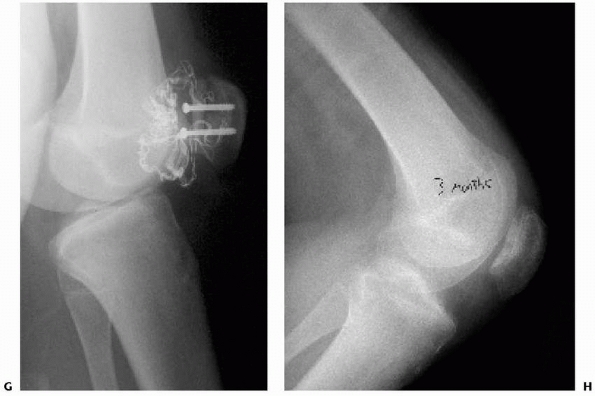

FIGURE 24-10

Type III tibial spine fracture in an 11-year-old male child treated with arthroscopic reduction and 3.5-mm cannulated screw fixation. Preoperative anteroposterior (A) and lateral (B) radiographs. Postoperative anteroposterior (C) and lateral (D) radiographs. |

hinged knee brace and maintain touch-down weight bearing for 6 weeks

postoperatively. Motion is restricted to 0 to 30 degrees for the first

2 weeks, 0 to 90 degrees for the next 2 weeks, and then full range of

motion. The brace is kept locked in extension at night. Radiographs are

obtained to evaluate maintainance of reduction and fracture healing (Fig. 24-10).